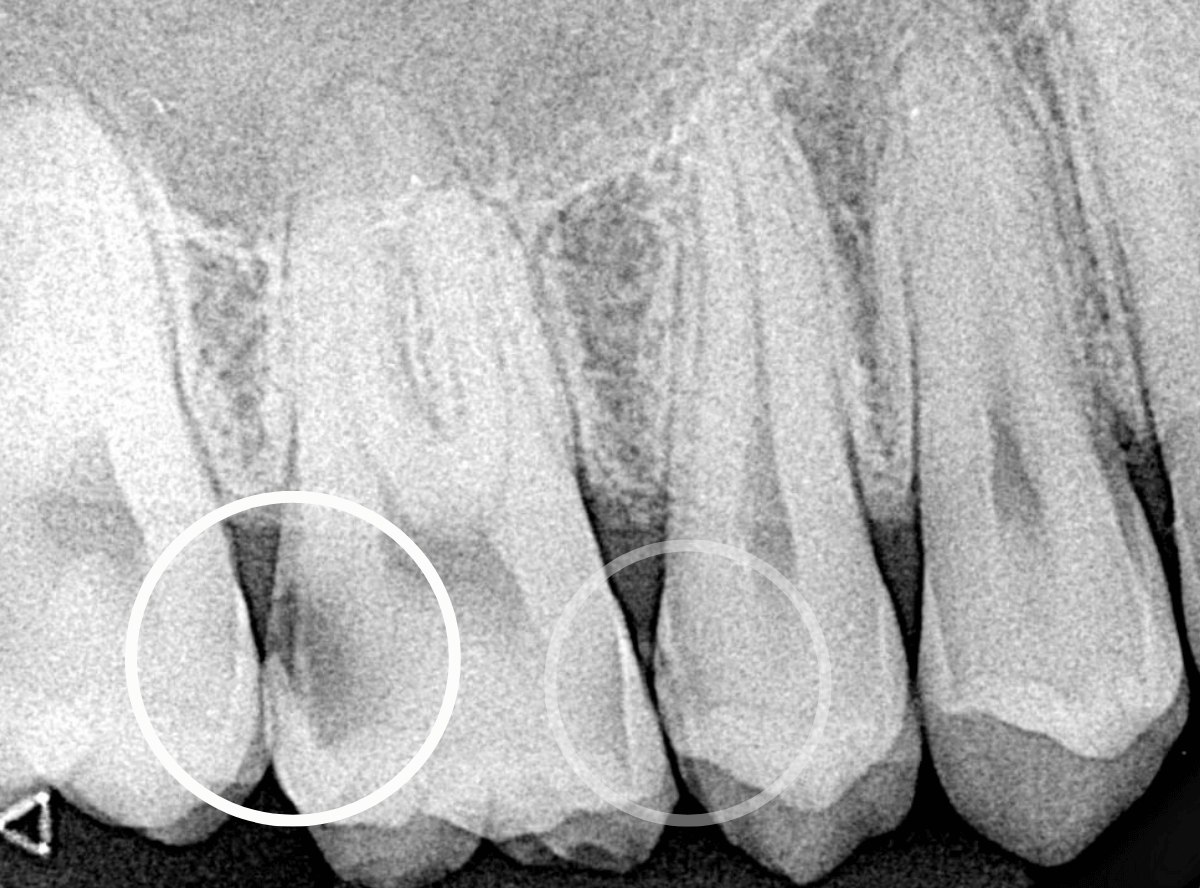

Case.22 痛みはないけど、歯のすきまから大きな虫歯

上の小臼歯の間が虫歯になっていた患者さんです。

症状はありませんし、見た目からも虫歯があるかはわかりませんでした。

レントゲン写真で確認します。

赤い線が虫歯、青い線が歯の神経です。

歯のすきまから両側に虫歯が大きく広がっているのが確認できます。

治療を開始します。

少し削ると、中からすぐに虫歯が出てきました。

ある程度、虫歯を除去したところで、う蝕検知液で確認します。

赤く染まっている部分が虫歯です。

まだまだ虫歯が中で残っている状況で、かなり深い虫歯なのが確認できます。

全ての虫歯を除去しました。

レントゲン写真からある程度確認出来ましたが、歯の神経スレスレまで虫歯が進行していました。

ここまで虫歯が進行していても、全く症状を感じない事も多いです。

そして、ある時急に痛みを感じるのです。

虫歯は急に進行しません。

治療後の定期検診で確実に食い止めましょう。